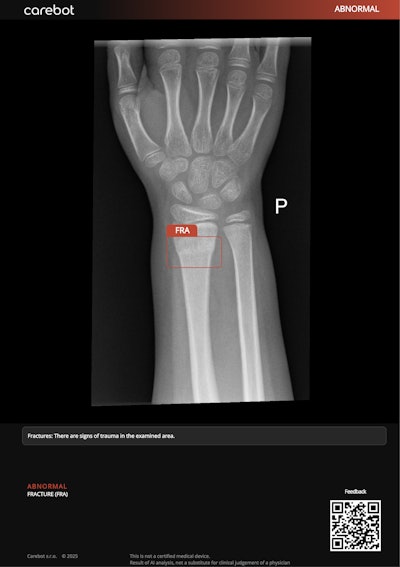

This includes the Carebot AI CXR for chest x-rays, an oncology portfolio that is complemented by a specialized mammography evaluation module, a suite of skeletal diagnostic tools, and specialized CT head and lung analysis systems.